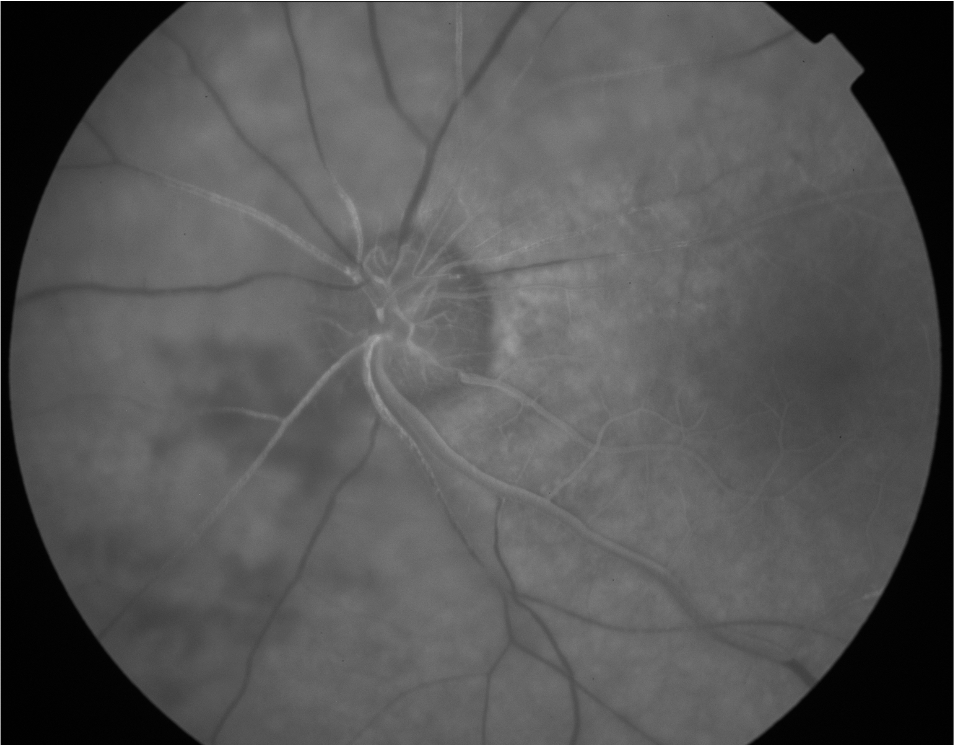

Practice the Basics: Hypofluoresence

Uveitis

Retina

Neuro-Ophthalmology

Ocular Oncology

Ocular Genetics

Pediatrics

Other